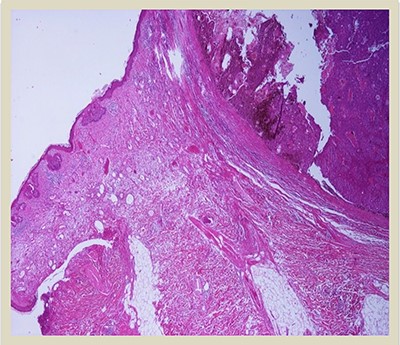

A 69-year-old man was admitted to our hospital with a nodular skin tumor of the back (Fig. 1). The patient had no ongologic history. We performed excisional biopsy that revealed collision tumor. The collision tumor consisted of mixed melanosquamous tumor (dermal squamomelanocytic tumor) together with BCC (Fig. 2). The BCC was superficial spreading. The mixed element contained squamous cell carcinoma of well/moderately differentiated and a neoplasm with melanotic characteristics, which due to cell atypia, presence of mitoses and high index of cell proliferation (Ki67: 80%) was described as melanoma (Fig. 3). Diagnosis of the melanotic and the squamous element was confirmed with immunohistochemistry (Figs 4 and 5).

H–E × 2: Collision tumor: in the right side of the photo is shown the dermal squamomelanocytic tumor component and in the left side the superficial basal cell carcinoma (H–E stain ×2 magnification).